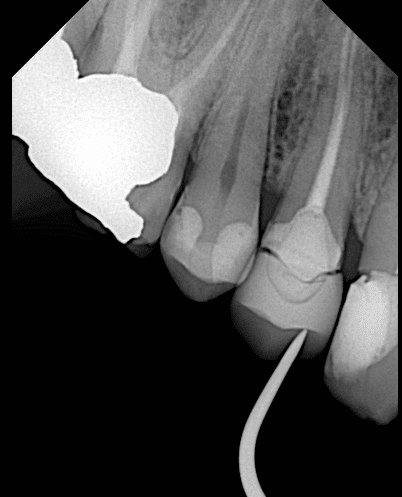

Firstly during trying the restoration I take x ray and see the overhang so I returned it to the lab to correct the overhang

Now the fitness is good